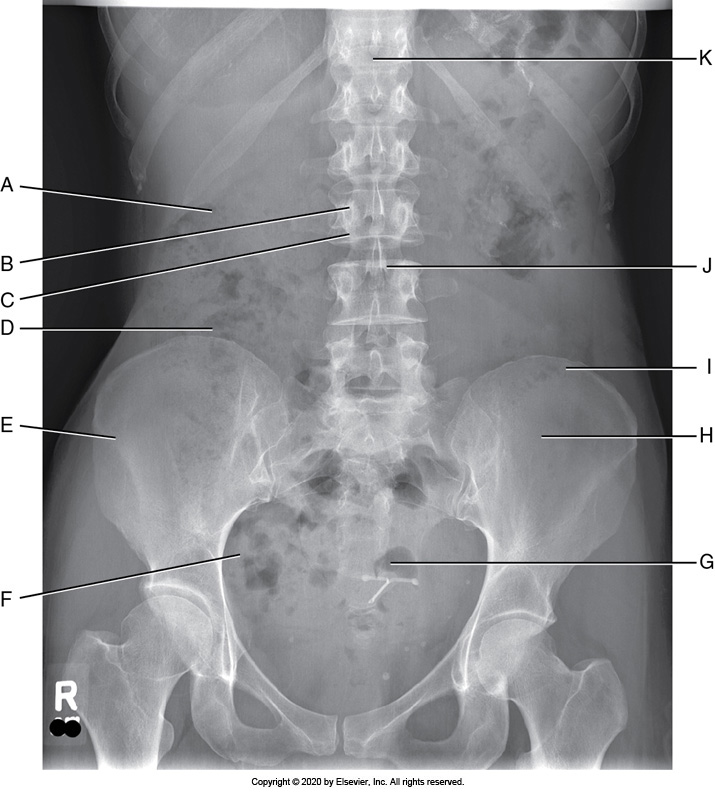

A supine AP abdomen projection with accurate positioning demonstrates the

1. outline of the psoas major muscles and kidneys.

2. symphysis pubis.

3. spinous processes aligned with the midline of the vertebral bodies.

4. long axis of the vertebral column aligned with the long axis of the collimated field.

1, 2, 3, and 4

3 and 4 only

1 and 2 only

1, 2, and 3 only

Identify the labeled anatomy "I" in the AP supine abdomen projection

Sacrum

Pedicle

Pubis symphysis

Iliac crest